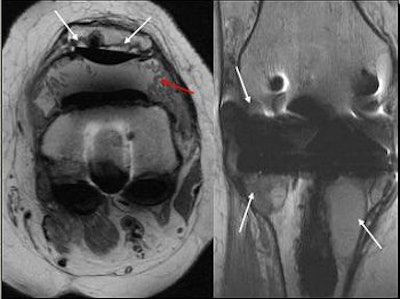

![]() |

| Edema in MCL from osteochondritis dissecans (OCD) and chrondomalacia. |

| Partially torn MCL with medial subluxation of medial meniscus. On the basis of MR measurements, no meniscal displacement was judged to be present in the supine 90° flexed position with external rotation or in the upright weight-bearing position. |